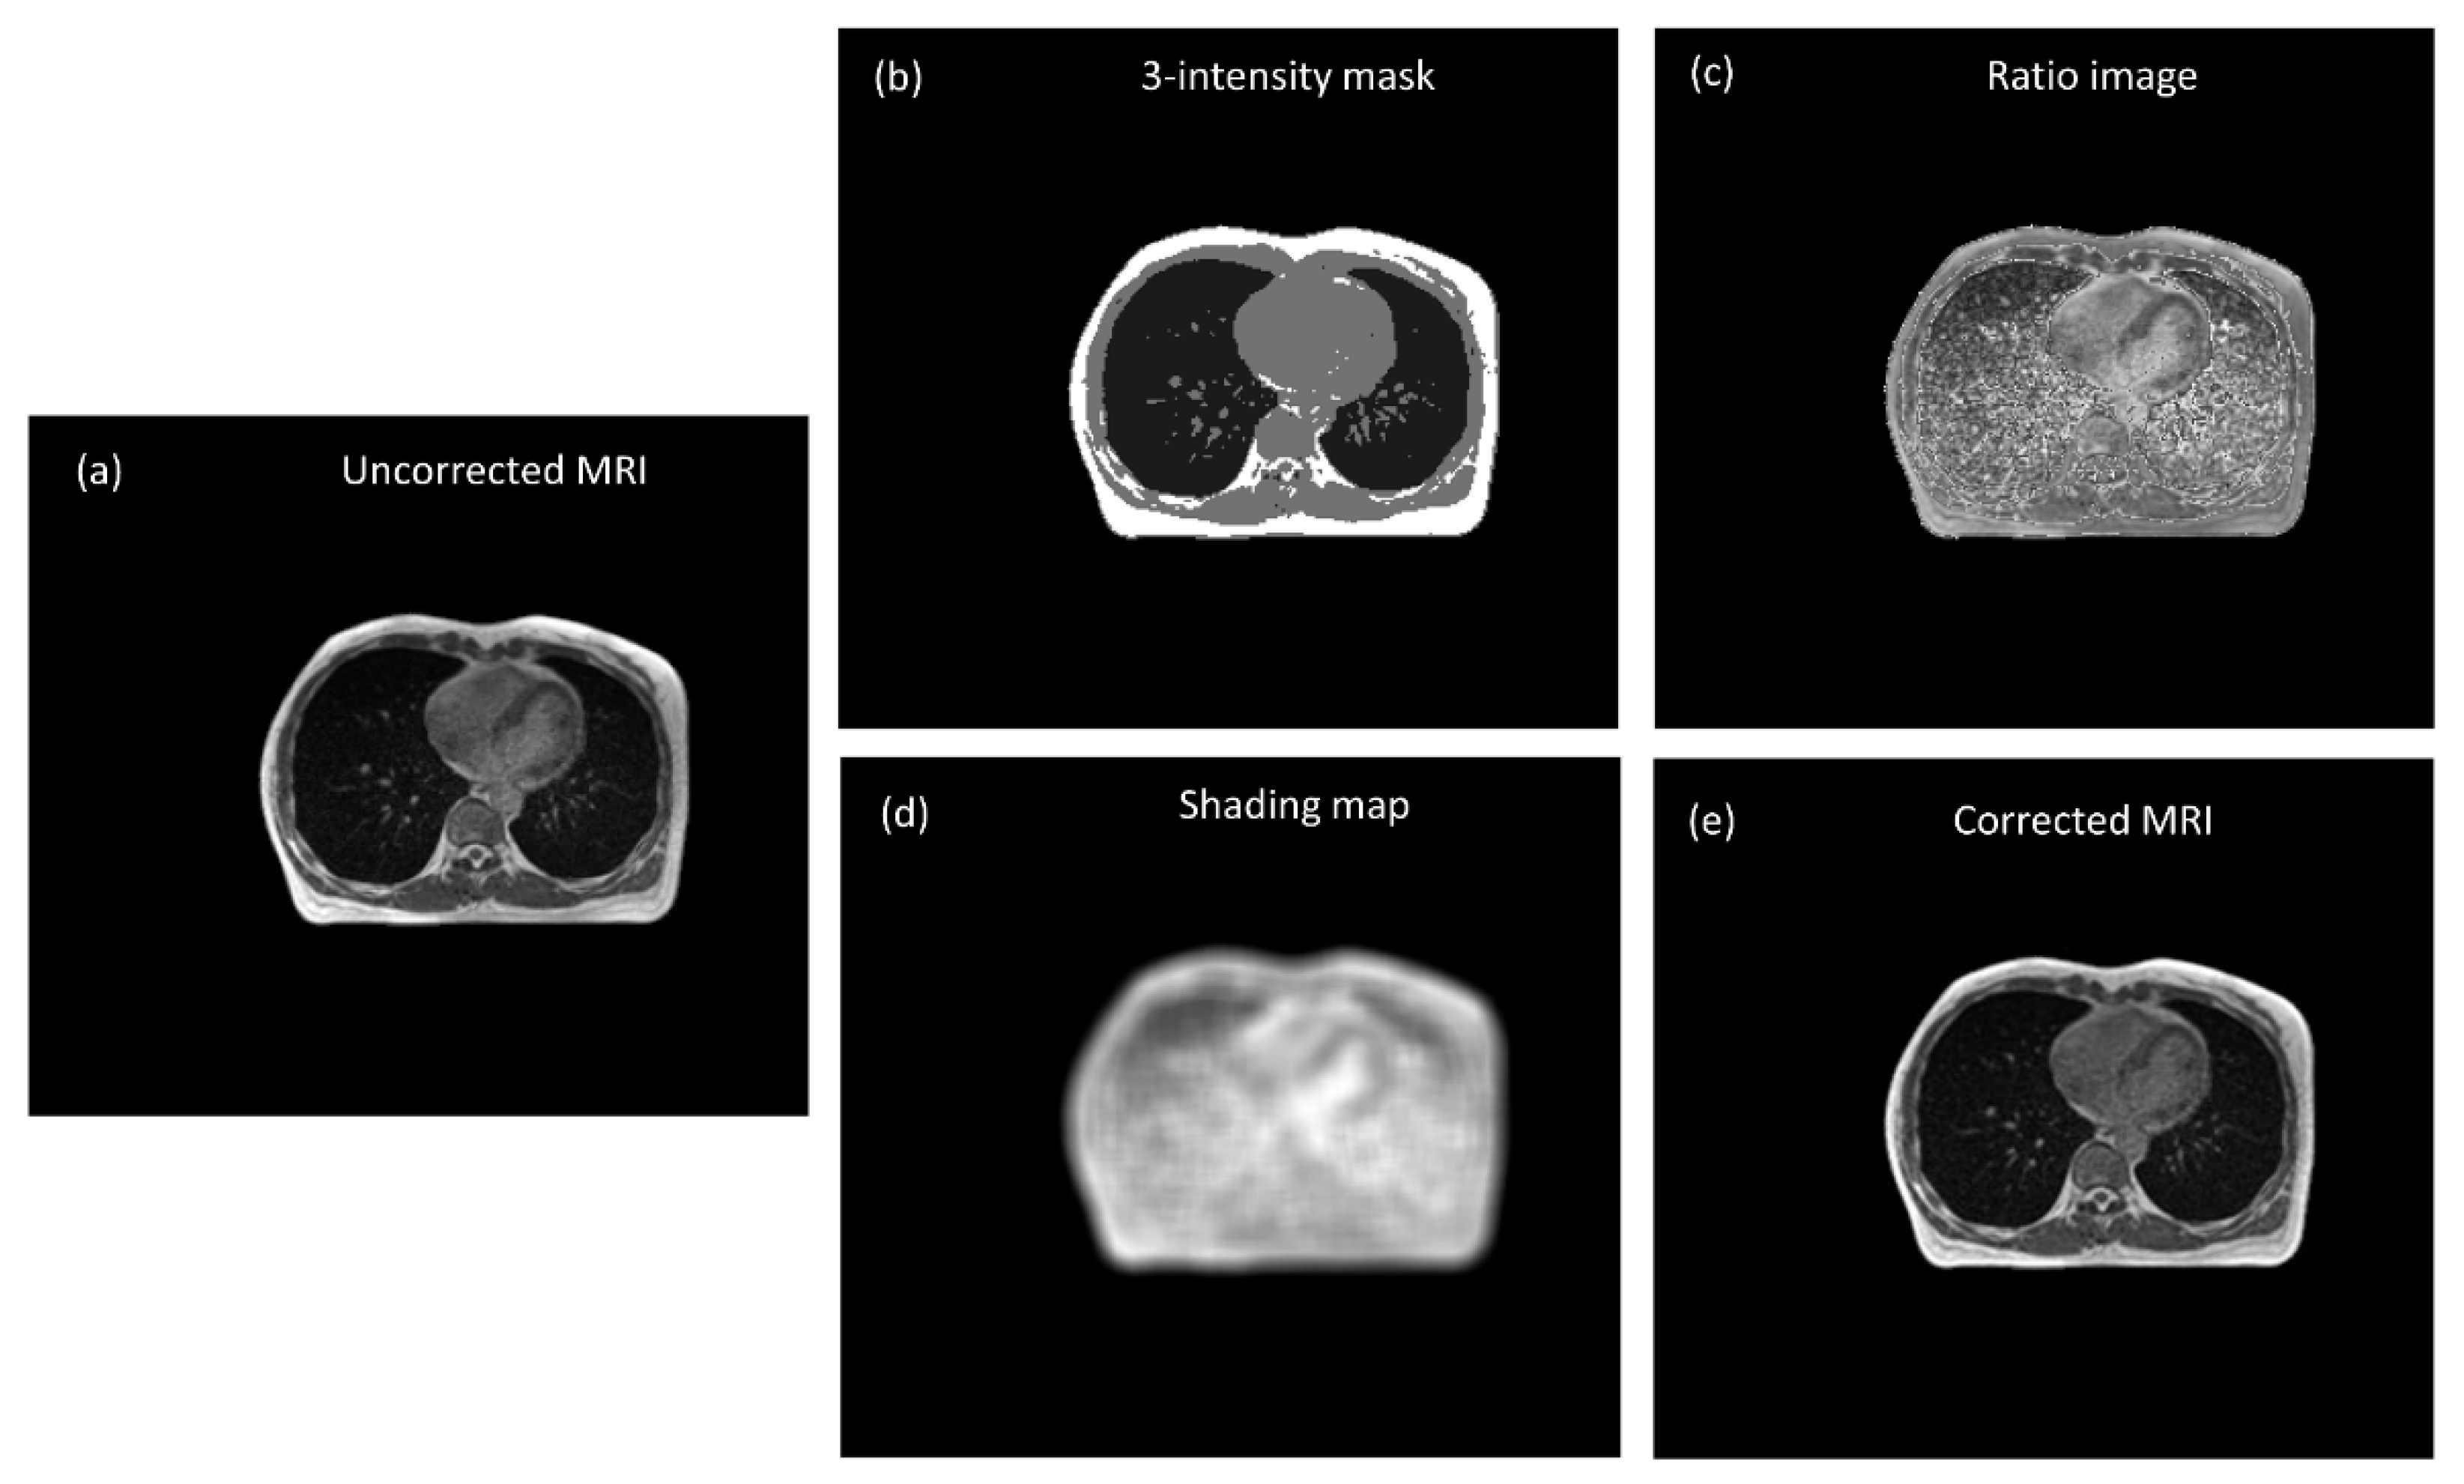

2.3. MRI Intensity Normalization